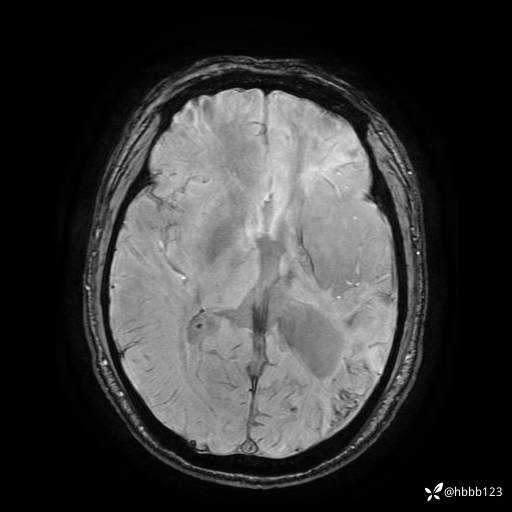

T2:

ADC: